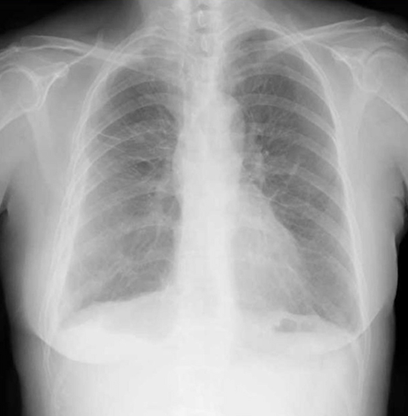

本症例のレントゲン所見としては所見:左右の横隔膜が平坦でところどころ尖っていることが確認できます。また右上肺野に横に走る線があり、その上部が黒いです(=嚢胞を疑う所見)。その他にもあちこちに嚢胞を疑わせる透過性亢進像あり

このような場合、疑うべき疾患は「嚢胞が多発する疾患」であり、女性だったらリンパ脈管筋腫症などになります。

上肺野:COPD

下肺野:肺線維症、COPD、リンパ脈管筋腫症(LAM)、ランゲルハンス細胞巨核球症など